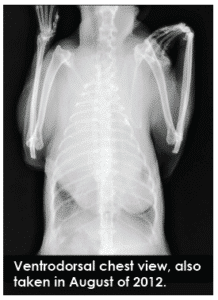

Miss Kitty first presented at our surgery at ten years of age. She had recently become quite breathless with any exertion. Her usual vet recommended euthanasia because thoracic radiographs revealed large growths on her lungs. Miss Kitty’s heart had been pushed sideways and could only be auscultated on the right side of her chest dorsally. An exact histopathological diagnosis was not pursued by the owners; however, homeopathic treatment was begun using her history, presenting symptoms, physical exam, and preliminary diagnostics.